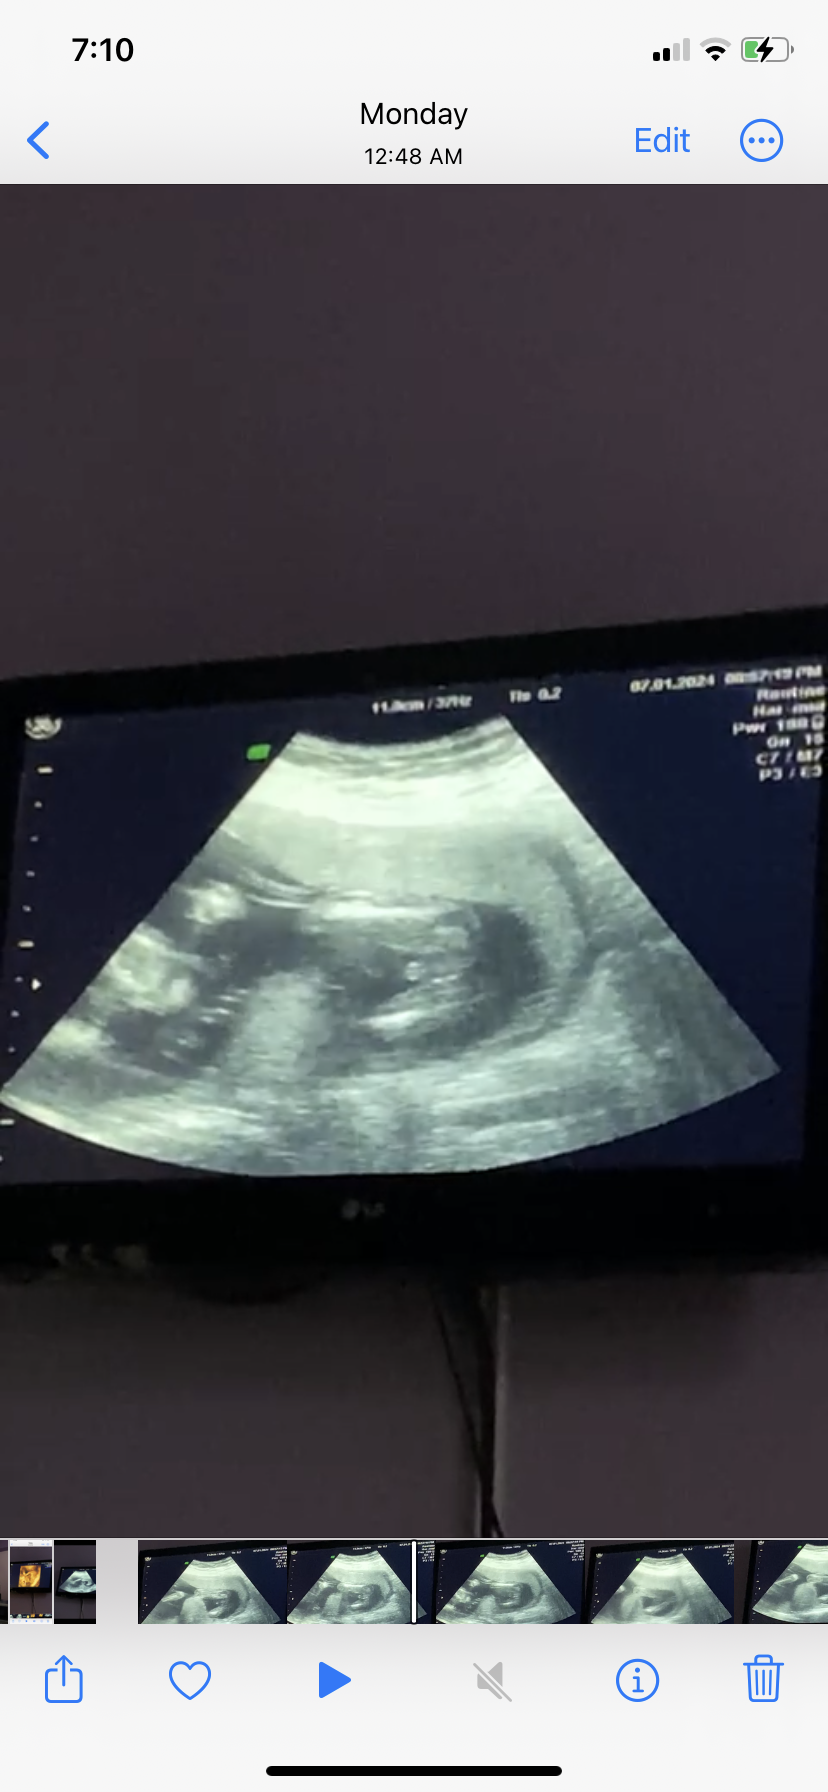

هل جنس المولود واضح من الصوره ولا ده حبل سري

هل يظهر جنس الجنين بشكل واضح في الاسبوع الثاني عشر ام ان هذا الحبل السري هل الجنين ذكر ام انثى...

هل جنين ذكر ام هذا الحبل السري

انا حامل بالاسبوع 13 ويوم1 . هل جنس المولود يبان الحين